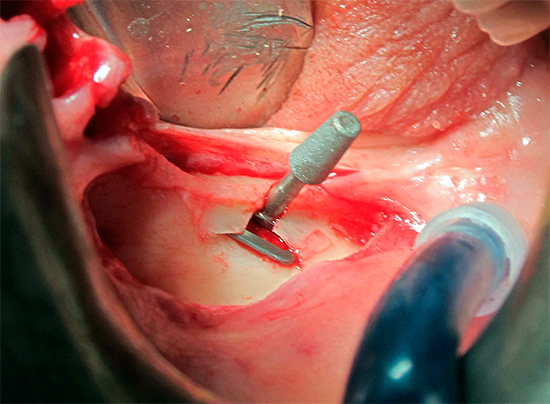

Na próxima etapa do implante basal, a instalação real dos implantes é realizada pelo método de punção ou incisão (ou imediatamente após a extração do dente). Uma punção torna possível realizar todo o procedimento sem suturar e é adequada para pessoas com gengivas enfraquecidas e inflamadas.

Com base nos dados simulados, modelos cirúrgicos individuais são desenvolvidos usando impressoras 3D. Geralmente, são estênceis de silicone sobrepostos na crista alveolar durante a cirurgia. Eles têm aberturas com um certo ângulo de inclinação através do qual os implantes são inseridos no osso.Assim, eles são instalados em um local precisamente calibrado, o que torna a operação menos arriscada e menos traumática.

- Implantes basais modernos são instalados de maneira minimamente invasiva, sem grandes incisões nos tecidos e suturas - por punção. Isso reduz o risco de complicações após a cirurgia, reduz e facilita a reabilitação para o paciente;